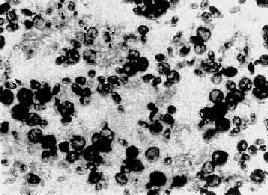

念珠菌引起的病变大致有三种:①在病变部经常有数量多少不等的单核细胞、淋巴细胞和中性粒细胞浸润,部分有小脓肿形成;②真菌侵犯的组织发生坏死,形成大小不等的坏死灶,其中炎性细胞较少;③肉芽肿性反应,这种病变比较少见,除一般炎性细胞浸润外,并有多核巨细胞和类上皮细胞形成结节状肉芽肿。以上病变可单独存在,也可同时发生。病变组织内并可见念珠菌的芽生孢子和假菌丝。念珠菌为圆形或椭圆形生芽的酵母样菌(图18-29),壁薄,直径约2~5μm。由芽管延长而形成的假菌丝细长而直(图18-30),有分隔,有时有少数分支。细长的假菌丝常侵入组织的深层,并可侵入血管(图18-31)。在组织切片内同时见到芽生孢子和假菌丝可诊断为念珠菌病。这些孢子和菌丝在HE染色切片中呈蓝色,如用革兰染色或镀银法则显示更为清晰。

图18-29 胃念珠菌病

胃溃疡表面的念珠菌芽生孢子